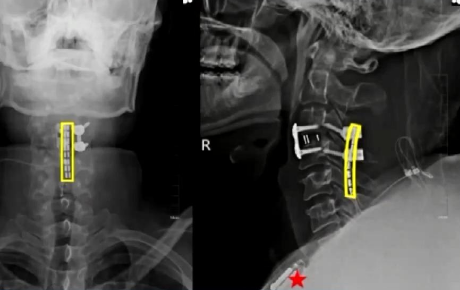

面对这一严峻挑战,医生吴敏飞团队作出了大胆尝试:将脊髓接口技术直接应用于患者颈髓段。吴敏飞介绍,颈脊髓损伤意味着大脑与脊髓之间的联系完全中断。而脊髓接口技术通过在损伤部位精准植入微型电极装置,激活并控制肢体运动神经元,使患者能够重新支配瘫痪的肢体活动。

手术取得圆满成功。经过两周持续优化的精准神经调控,刘博奇的四肢肌力显著恢复。三个月后,团队为他量身定制了“脊髓接口+外骨骼机器人”协同康复方案。在脊髓接口的精准调控与外骨骼机器人的辅助支撑下,刘博奇成功迈出了受伤后的第一步。